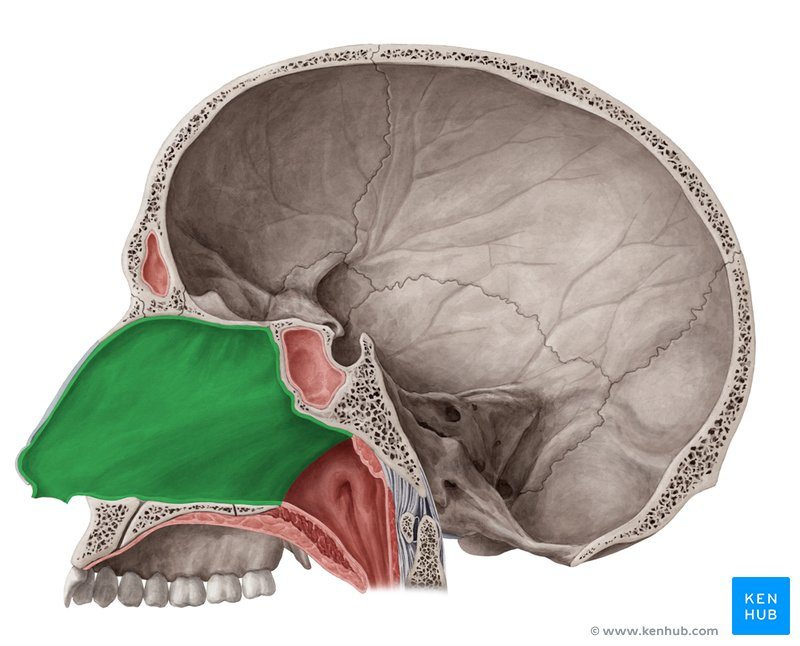

Nasal Cavity

Uppermost part of respiratory system; functions to warm and moisten air